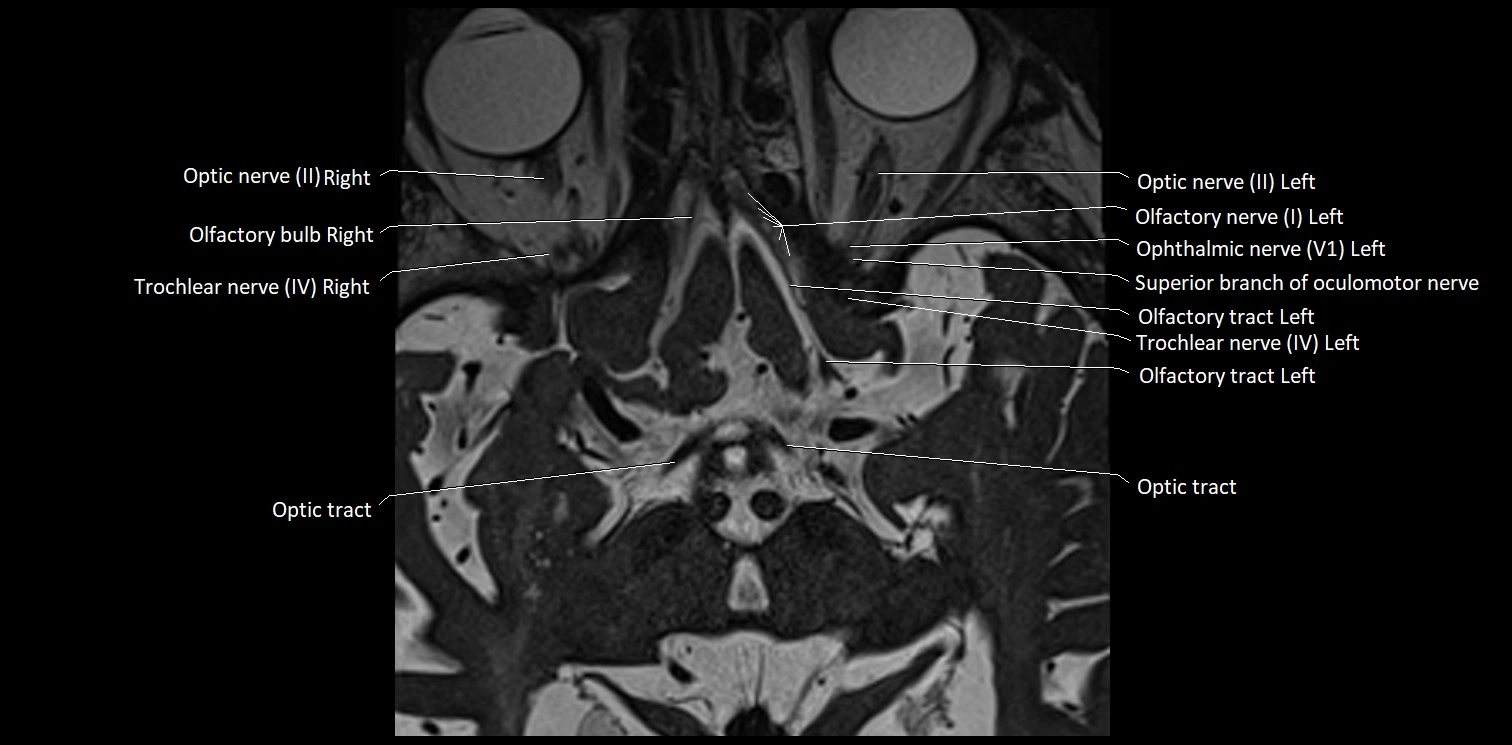

MRI Appearance

• The abducens nerve is a small, thin, linear structure

• Best visualized on high-resolution T2-weighted 3D MRI sequences (e.g., FIESTA or CISS)

• Seen as a hypointense (dark) line running from the brainstem at the pontomedullary junction, traversing the prepontine cistern, and entering Dorello’s canal under the petrosphenoidal ligament, then into the cavernous sinus, and finally the orbit

• May be challenging to visualize in standard MRI due to its small size

• Pathology may be inferred by absence, displacement, or enhancement of the nerve

MRI images

image